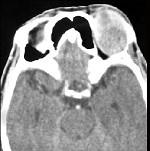

问题 男性45岁,左眼疼痛伴视力下降一个多月,左眼明显外突,CT扫描如图所示,最可能诊断为 ( )

选项 A、眶内结核 B、眶内转移瘤 C、眶内血管瘤 D、眶内纤维瘤 E、左侧眶内炎性假瘤

答案 E